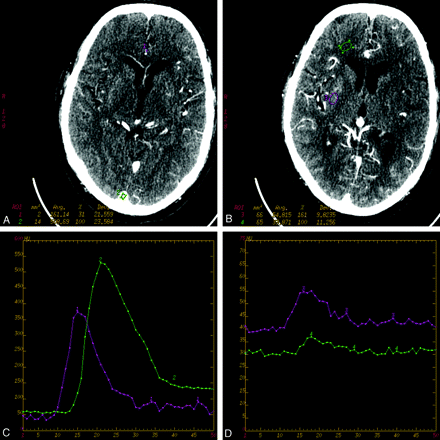

The regions of interest (ROI) for an arterial input (ACA) and venous output (sagittal sinus) (A) and for gray matter and white matter (B). The corresponding time-concentration curves are presented in C, in which curve 1 indicates the artery and curve, 2 the vein, and in D, in which curve 3 indicates gray matter and curve 4, white matter.

The arterial input curve was determined from an anterior cerebral artery (ACA), and the venous output, from the superior sagittal sinus. For the vessel analyses, the sections used were the ones through which the vessel traveled perpendicularly, as is the convention during clinical CTP analysis. This permitted us to achieve “pure” blood curves while avoiding partial volume effects from adjacent tissues.

A time-enhancement curve (or delta-HU curve) was constructed for each region of interest (Fig 1C, -D) and fitted with a gamma variate function by using an automated Marquardt-Levenberg nonlinear fitting technique to remove the effects of noise and subjectivity from determination of peak opacification. Peak opacification was then calculated by using the fitted parameters.